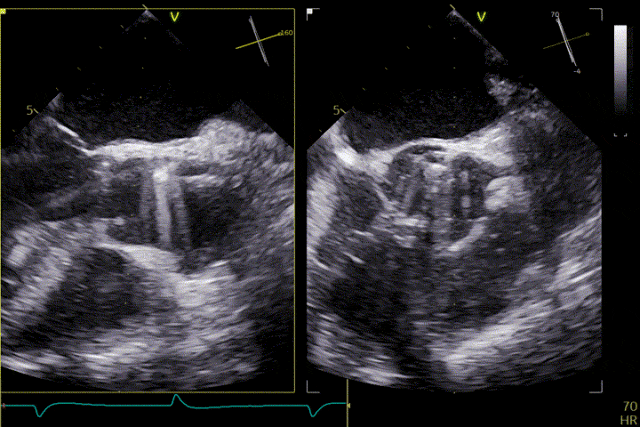

術前超聲

患者主動脈瓣重度反流糾正,術后無反流、無瓣周漏。術后心臟彩超顯示人工生物瓣啟閉良好,平均跨瓣壓差2mmHg,流速正常。患者恢復情況良好,心功能較術前有了明顯改善。